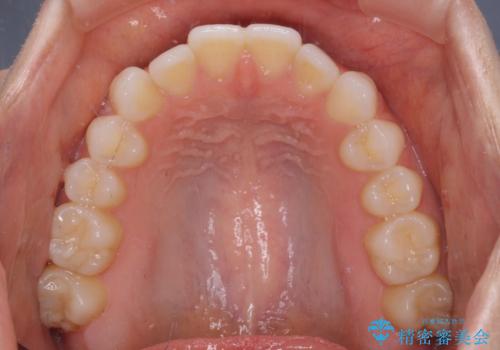

上下前歯が接触しない オープンバイトをインビザラインで改善

- 前歯の上下スペースによる食べにくさを気にして来院された患者様です。

インビザラインにより上下の前歯の隙間を閉じていくこととしました。

上下の奥歯を圧下させるようにすることで、前歯を接触させるように計画しました。

上下の隙間に舌が入り込むことがオープンバイトの原因であったため、舌の筋肉のトレーニングも並行して行い、後戻りの抑制を図りました。